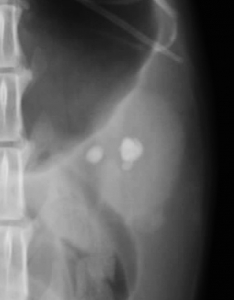

下のレントゲン像の黄色の縁で囲んだ目立たない結石は画像でこそ目立ちませんが、急性の尿管閉塞を生じている尿管結石です。尿管閉塞というのはお腹の中で腎臓から膀胱をつなぐ細い尿管で生じます。尿路閉塞として一般的な膀胱結石による尿道閉塞とその仕組みは同じです。

尿道結石は尿道という体の外に出る管での問題ですから、体外から結石除去を試みることができます。ところが尿管閉塞はお腹の中ですから手術以外の方法で結石に到達することができません。内科的に結石を尿管から膀胱へ落とすためには利尿薬などを組み合わせた点滴療法で自然排泄を図りますが、単独では決して確実な方法ではありません。